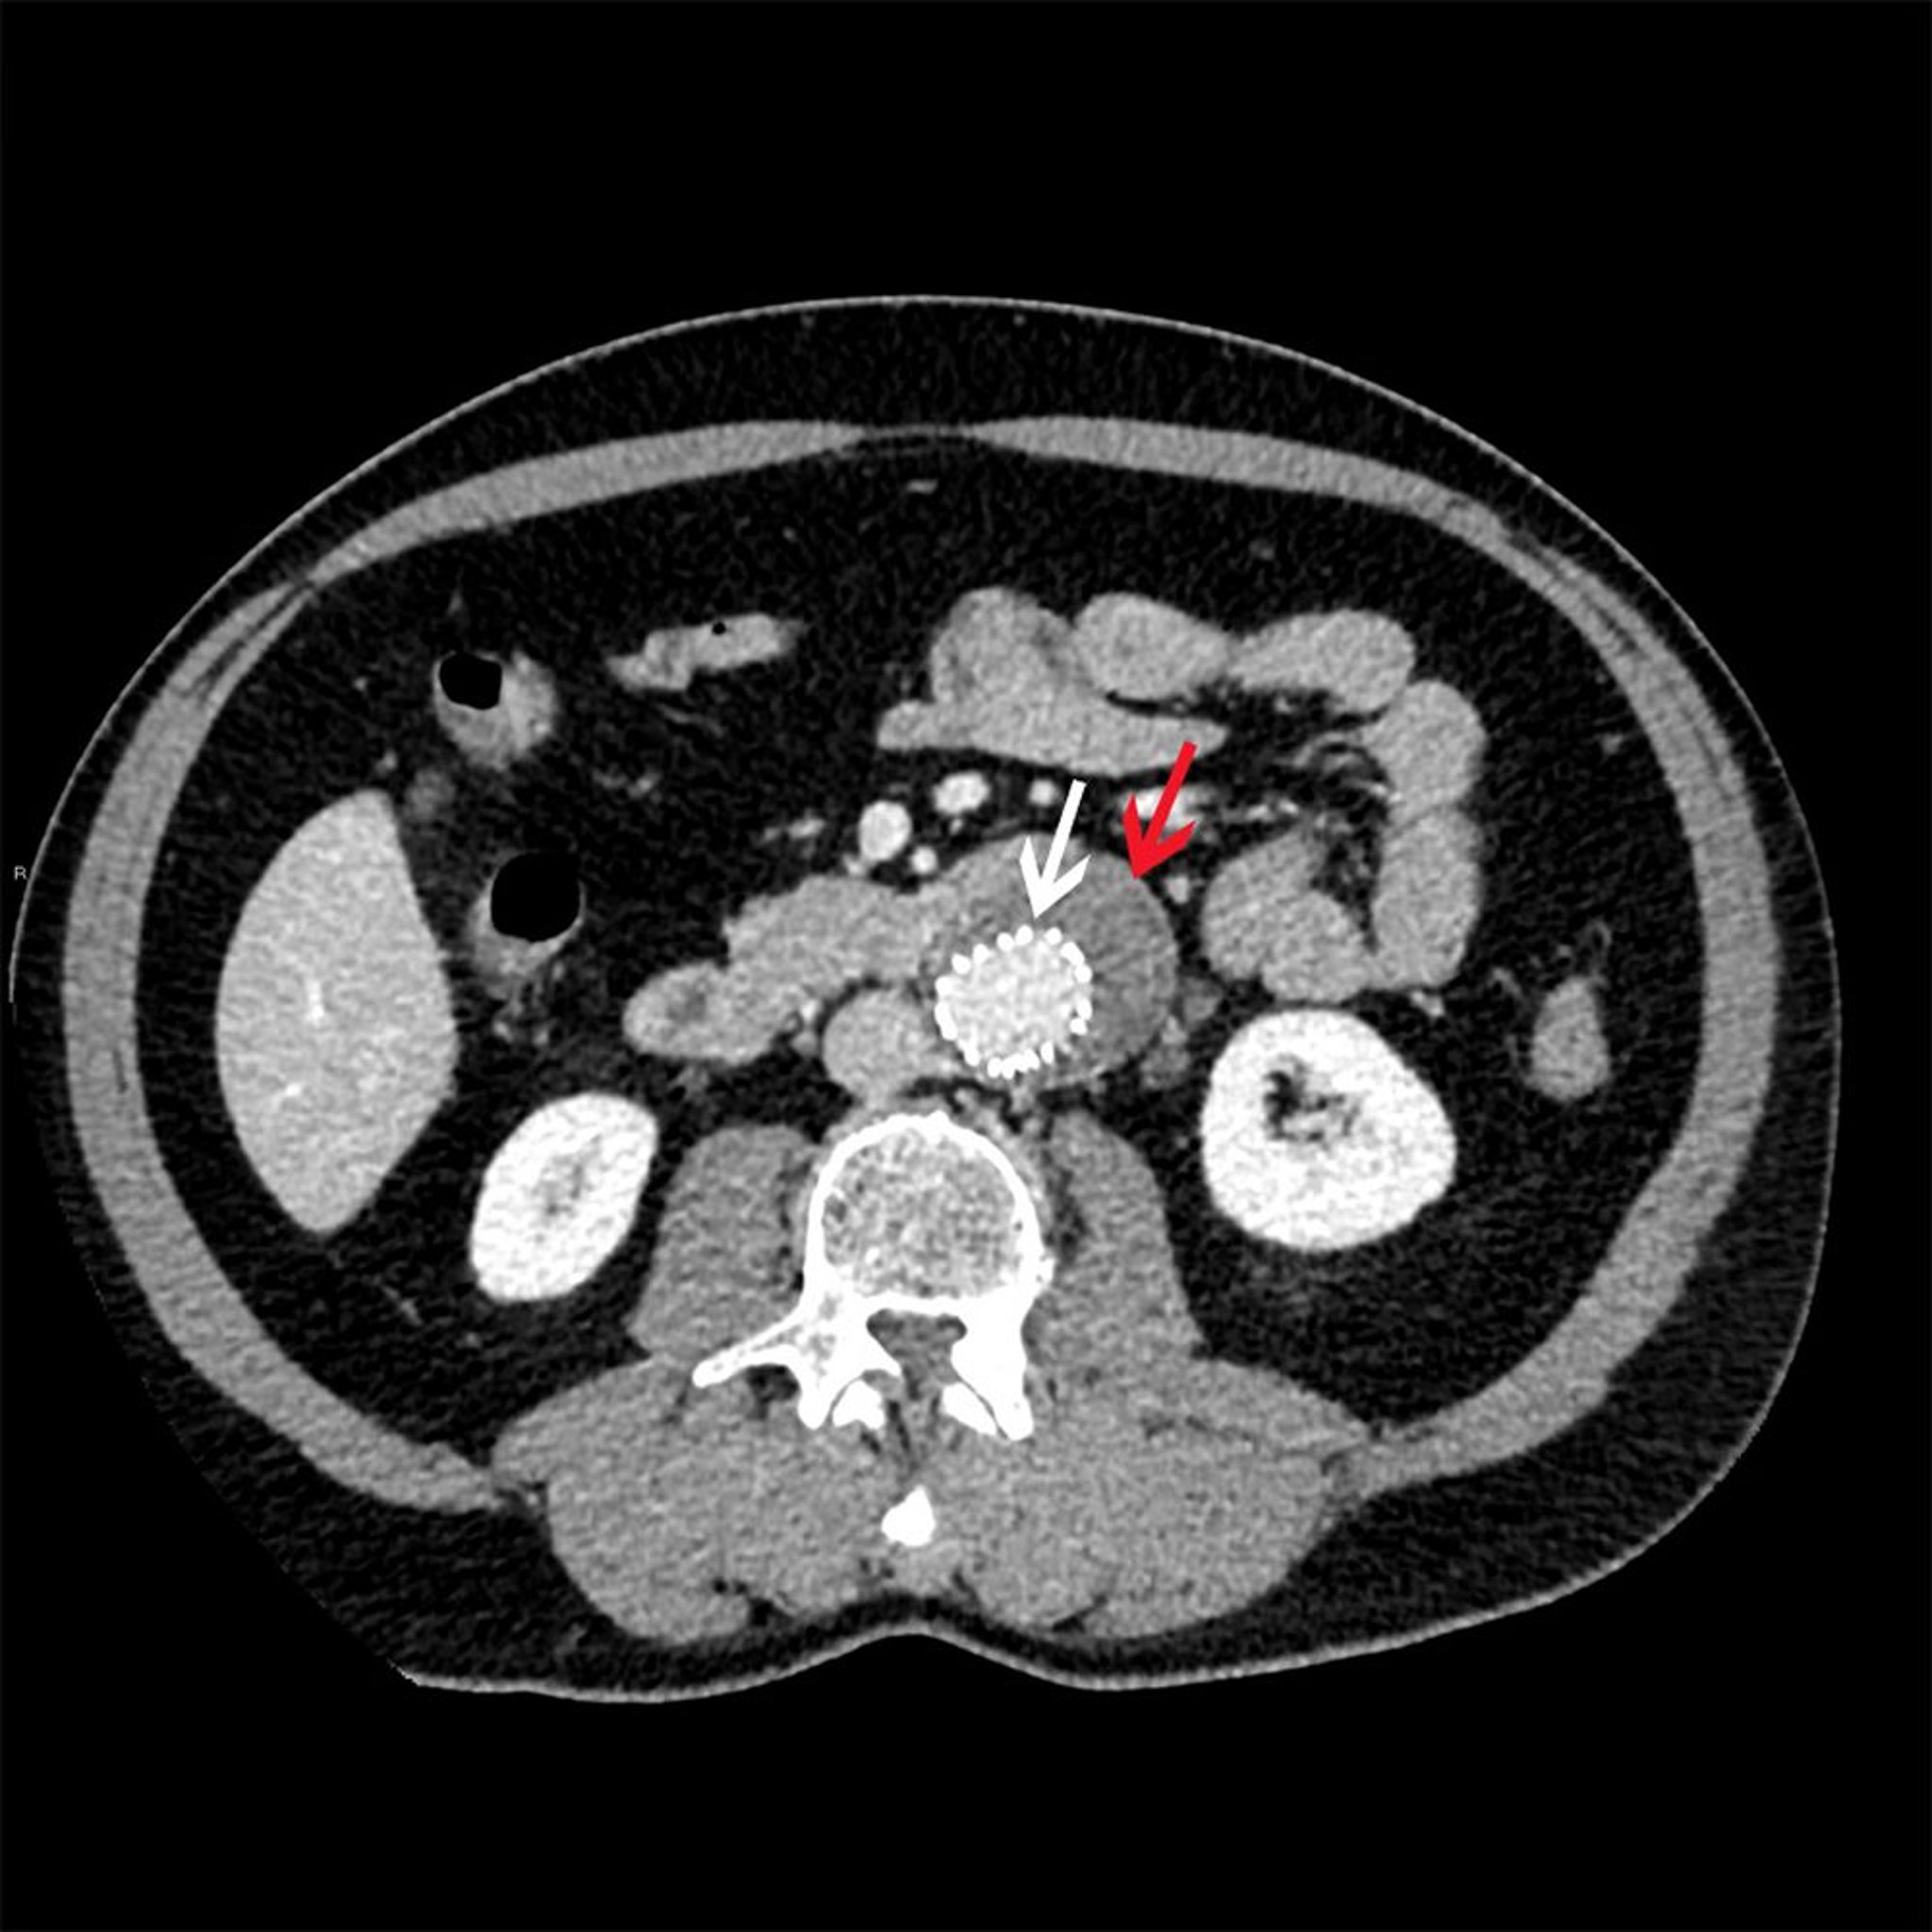

Stent endovascolare

La freccia bianca mostra uno stent endovascolare all'interno di un aneurisma addominale (freccia rossa).